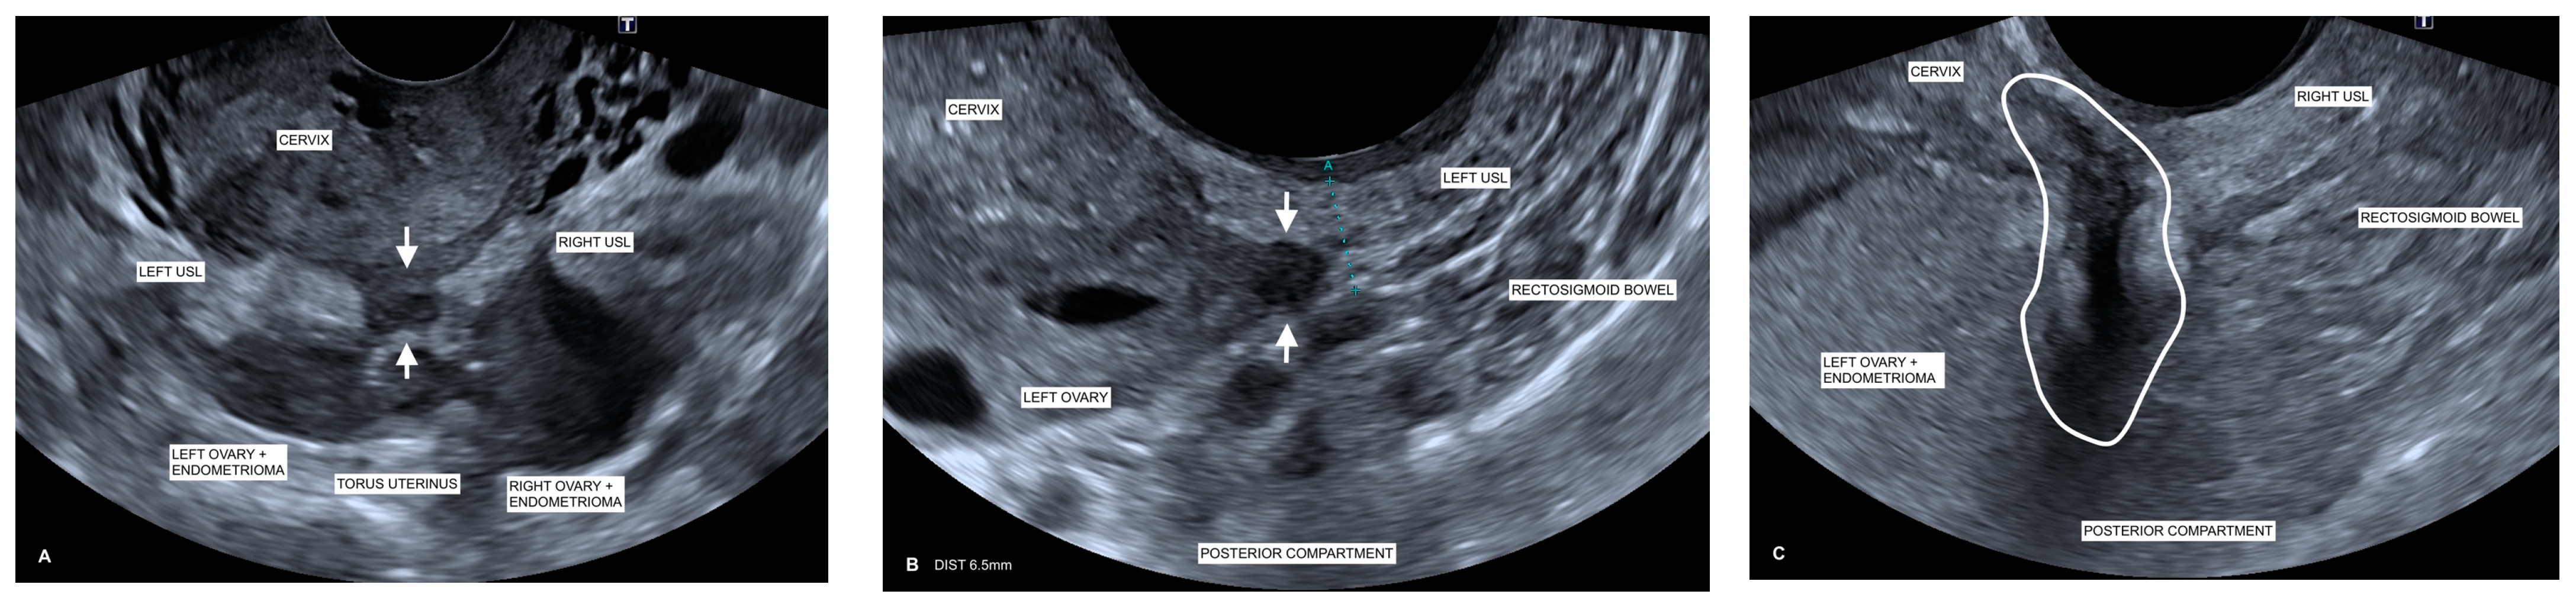

2.5.1. Image Acquisition

- Maple, S.; Chalmers, K.J.; Bezak, E.; Henry, K.; Parange, N. Ultrasound Characteristics and Scanning Techniques of Uterosacral Ligaments for the Diagnosis of Endometriosis. J. Ultrasound Med. 2022, 42, 1193–1209. [Google Scholar] [CrossRef] [PubMed]

- Leonardi, M.; Condous, G. A pictorial guide to the ultrasound identification and assessment of uterosacral ligaments in women with potential endometriosis. Australas. J. Ultrasound Med. 2019, 22, 157–164. [Google Scholar] [CrossRef]